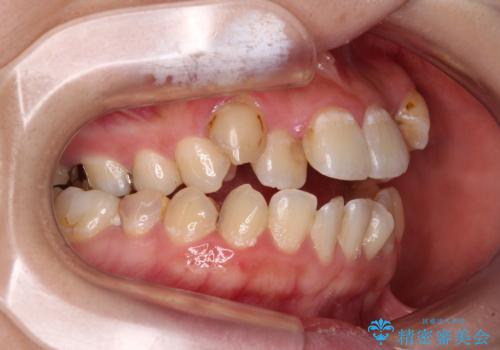

- 上下の歯が非接触であり、八重歯やむし歯を気にして来院された患者様です。

下顎骨の左右偏位はあるものの、上顎骨幅が相対的に狭い状態であったので、奥歯の咬み合わせが非常に乱れていました。

急速拡大装置により上顎骨幅を側方に拡大し、それを利用して八重歯を歯列に納めることにしました。